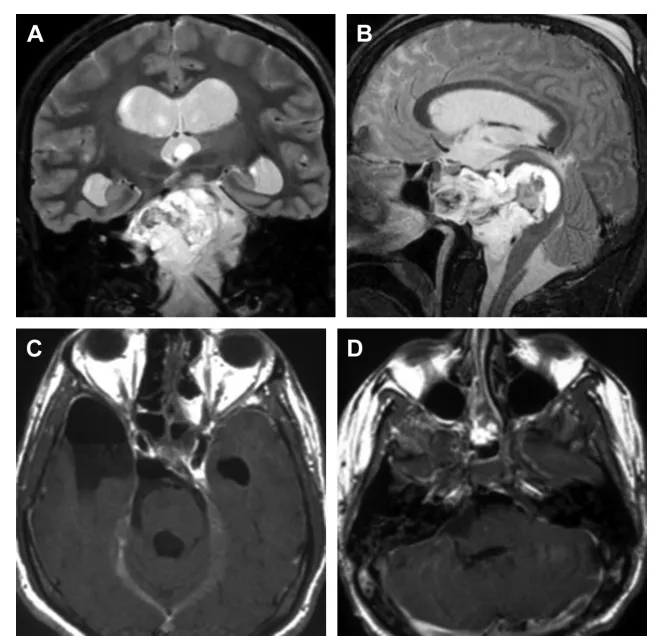

本例复杂脊索瘤病例肿瘤位于关键解剖区域——斜坡上部,且已...